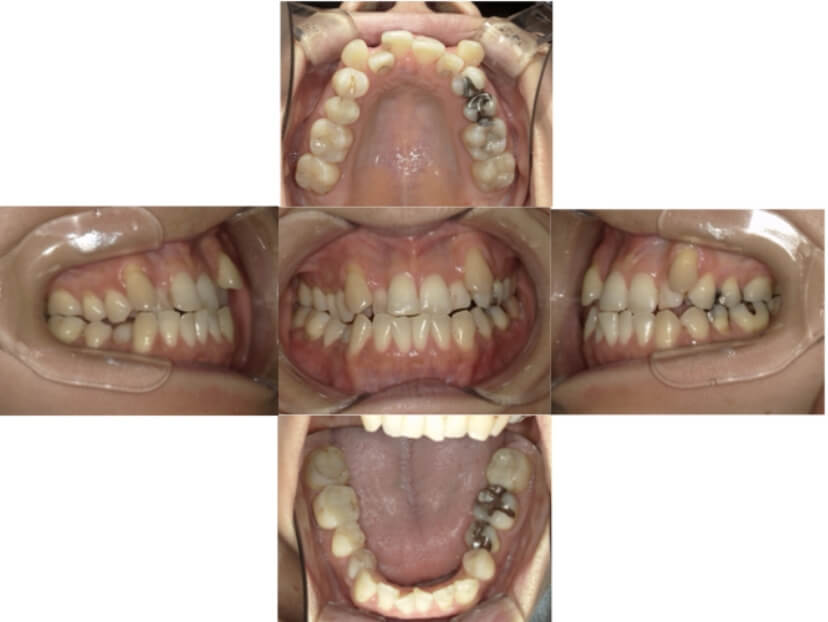

BEFORE

AFTER

症例5

開咬

抜歯

ブラケット矯正

症例解説

前歯部開咬(上下の前歯が咬んでいない)のケースです。

装置はラビアル(上下表側)で、上下顎の小臼歯を4本抜歯で治療を行いました。抜歯スペースを利用して上下前歯の後方移動を行い、顎間ゴムを使って上下前歯の開咬の改善を行っています。

主訴 前歯の咬んでないので食事がしづらい。

年齢・性別 23歳 女性

お住まいの地域 東京都品川区

治療方針 抜歯スペースを利用して上前歯の叢生(ガタガタ)および開咬の改善

抜歯部位 上下顎左右第一小臼歯

使用装置 ラビアル(上下表側)、顎間ゴム

治療期間 1年11か月

治療回数 14回

リテーナー クリアリテーナー